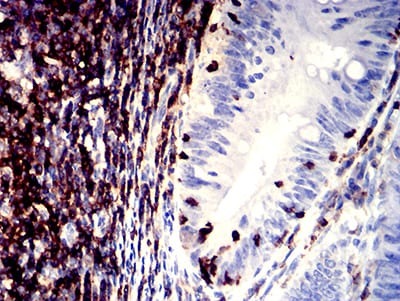

| IHC | 1/200 - 1/1000 |

Product Image |